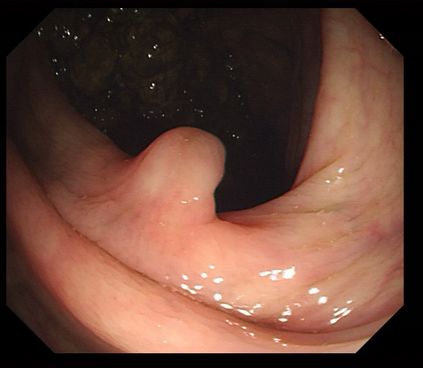

Polyps are early cancer indicators, so assessing occurrences of polyps and their removal is critical. They are observed through a colonoscopy screening procedure that generates a stream of video frames. Segmenting polyps in their natural video screening procedure has several challenges, such as the co-existence of imaging artefacts, motion blur, and floating debris. Most existing polyp segmentation algorithms are developed on curated still image datasets that do not represent real-world colonoscopy. Their performance often degrades on video data. We propose a video polyp segmentation method that performs self-supervised learning as an auxiliary task and a spatial-temporal self-attention mechanism for improved representation learning. Our end-to-end configuration and joint optimisation of losses enable the network to learn more discriminative contextual features in videos. Our experimental results demonstrate an improvement with respect to several state-of-the-art (SOTA) methods. Our ablation study also confirms that the choice of the proposed joint end-to-end training improves network accuracy by over 3% and nearly 10% on both the Dice similarity coefficient and intersection-over-union compared to the recently proposed method PNS+ and Polyp-PVT, respectively. Results on previously unseen video data indicate that the proposed method generalises.